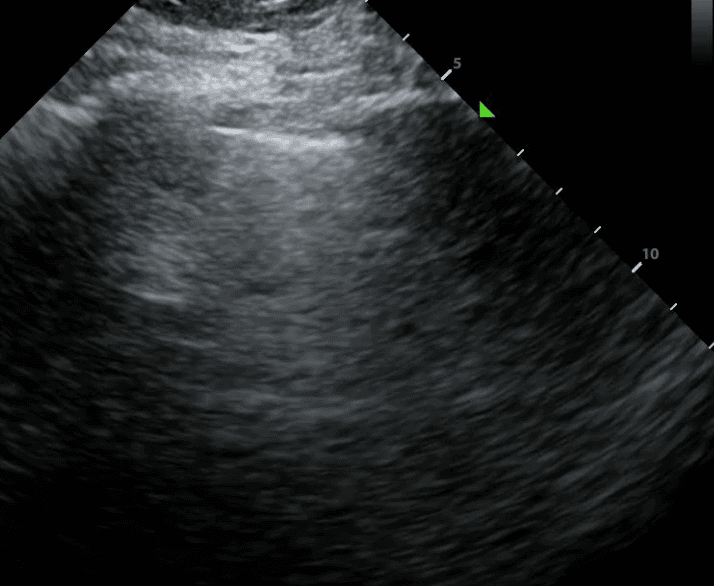

The first step in the 2D assessment of lung sliding is to identify your landmarks. Ribs are discerned at the far left and far right of the above image. They appear as bright (ie. hyperechoic) structures with shadowing below them. In between the rib shadows, you should see the pleural line. This appears as a luminous hyperechoic line. When lung sliding is present, the pleural line has a characteristic shimmering motion that some refer to as the appearance of “ants on a log.”